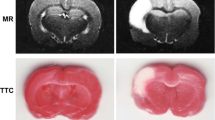

BMSCs modified with XIAP attenuates brain pathological injury in CP rats

The pathological morphology of brain tissues in rats was observed by HE staining. The results of which suggested that in rats of the sham group, brain tissue structure was normal, interstitial edema was not observed, cytoplasm was abundant and nucleus were clearly visible. In rats of the CP group and the CP + PBS group, the brain tissue structure was destroyed, white matter was disordered, which was presented with multiple irregular cystic cavities, cell swelling, degeneration, disordered arrangement, inflammatory cell infiltration and local round softening foci. In rats in the CP + BMSCs group and the CP + NC-BMSCs group, the degree of cell swelling was reduced, inflammatory infiltrating cells were decreased, and cystic degeneration was decreased. In rats of the CP + XIAP-BMSCs group, the pathological degree of brain tissue was further alleviated and the cells were arranged neatly (Fig. 5a).